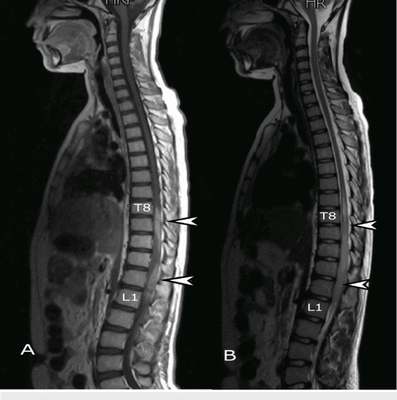

о Позвоночная локализация - Шейный отдел (50%, в основном С2)> грудной отдел (Т8 > Т4 > другие уровни) > поясничный отдел >> крестец

4. МРТ при остеохондроме позвоночника:

• Т1-ВИ:

о Гиперинтенсивность центральной зоны (костного мозга), окруженная гипоинтенсивным кортикальным слоем

о Гипо-/изоинтенсивный хрящевой колпачок, образованный гиалиновым хрящом

• Т2-ВИ:

о Изо- или гипоинтенсивность центральной зоны (костного мозга), окруженная гипоинтенсивным кортикальным слоем

о Гиперинтенсивный хрящевой колпачок, образованный гиалиновым хрящом

• Т1-ВИ с КУ:

о Может отмечаться периферическое усиление и усиление сигнала перегородок в хрящевом колпачке

о МРТ позволяет оценить размеры хрящевого колпачка, состояние смежных нервных и костно-мышечных структур

(Слева) Аксиальный срез, Т1-ВИ: костномозговое пространство остеохондромы, расположенное в просвете спинномозгового канала, с преимущественно гипоинтенсивным хрящевым колпачком, вызывающим стеноз шейного отдела позвоночника и сдавление спинного мозга.